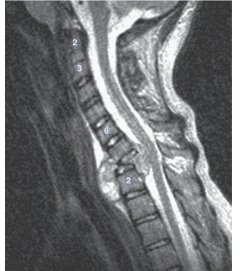

-Refer to the figure. What imaging modality and view is this?

A) Lateral radiograph

B) Sagittal CT

C) Coronal MRI

D) Sagittal MRI

7

-Refer to the figure. Observe the spinal canal. The spinal canal would be described on this patient as:

A) Patent at all levels

B) Effaced at all levels

8

-Refer to the figure. What modality and sequence is this? Hint: Remember to look where you expect to see fluid.

A) T1-weighted CT

B) T2-weighted CT

C) T1-weighted MRI

D) T2-weighted MRI

9

-Refer to the figure. What vertebrae has undergone complete destruction?

A) Seventh cervical vertebra

B) Eighth cervical vertebra

C) First thoracic vertebra

D) Second thoracic vertebra